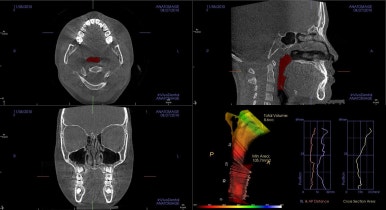

부산소아교정 키다리아저씨치과에서는 우측 사진처럼 호흡기의 구조를 세심히 판단하고 들어가요.

(호흡기 구조까지 알려주는 치과는 아마 거의 없을거에요.)

이번 환자분의 경우 콧속(비강)이 매우 좁아 구조적으로 코로 호흡하기가 힘든 상황입니다.

호흡이 잘 안되면 연쇄적으로 턱뼈의 성장에 영향을 줘요. 특히 윗니-코주위까지의 위턱뼈를 3차원적으로(앞뒤-좌우) 좁아지게 만듭니다.